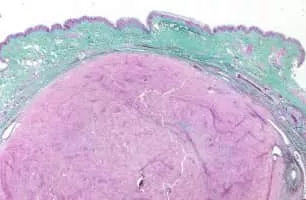

Dermatopathology photograph

Dermatopathology is a joint subspecialty of dermatology and pathology or surgical pathology that focuses on the study of cutaneous diseases at a microscopic and molecular level. It also encompasses analyses of the potential causes of skin diseases at a basic level.